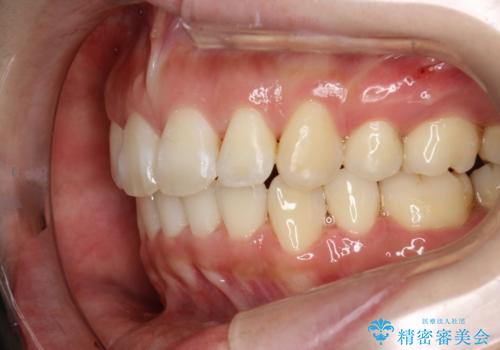

矯正歯科治療 → 叢生(でこぼこ・八重歯)

フルリンガル矯正 非抜歯でガタつきを整える